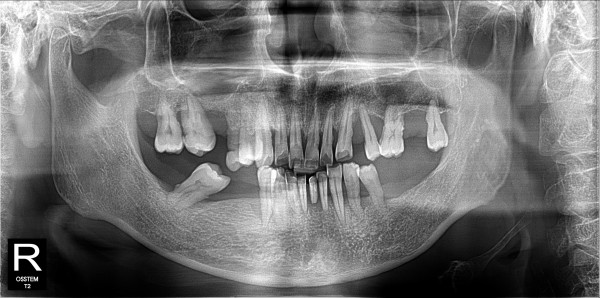

구치부 임플란트 최고관리자 0건 23-11-07 18:31 본문 구치부 임플란트 + 전치부 크라운 목록 이전글구치부 임플란트 23.11.07 다음글구치부 임플란트 23.11.07 댓글목록 0 댓글목록 등록된 댓글이 없습니다.